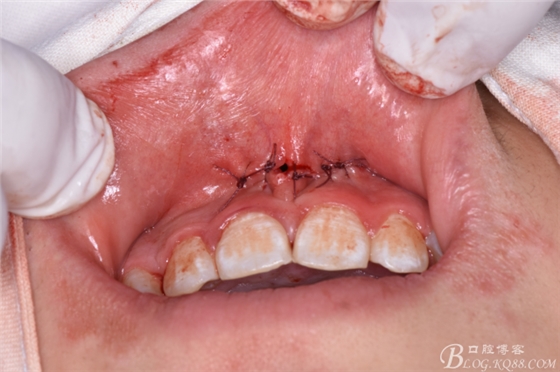

圖17.放膠質(zhì)銀

圖18.拔除大多生牙

圖19.縫合創(chuàng)口